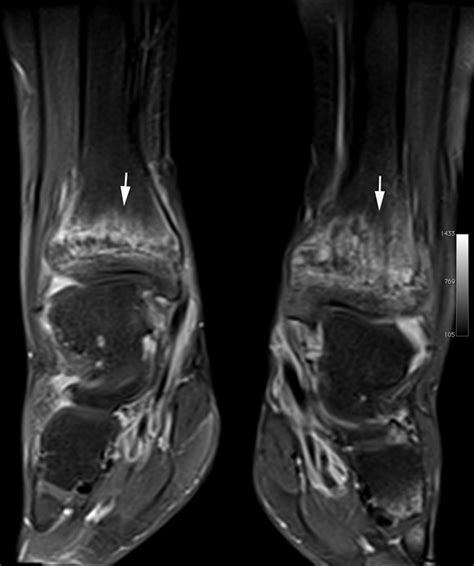

Diagnostic Approach and Imaging

Diagnosing Chronic Multifocal Osteomyelitis is a process of exclusion. Because there is no single laboratory blood test that confirms the diagnosis, physicians rely on a combination of clinical findings, imaging, and, in some cases, a bone biopsy to rule out other more serious conditions like malignancy or bacterial osteomyelitis.

MRI (Whole Body) The gold standard for identifying multifocal lesions without radiation exposure.

💡 Note: A whole-body MRI is highly recommended by specialists to identify asymptomatic lesions that might otherwise go undetected.